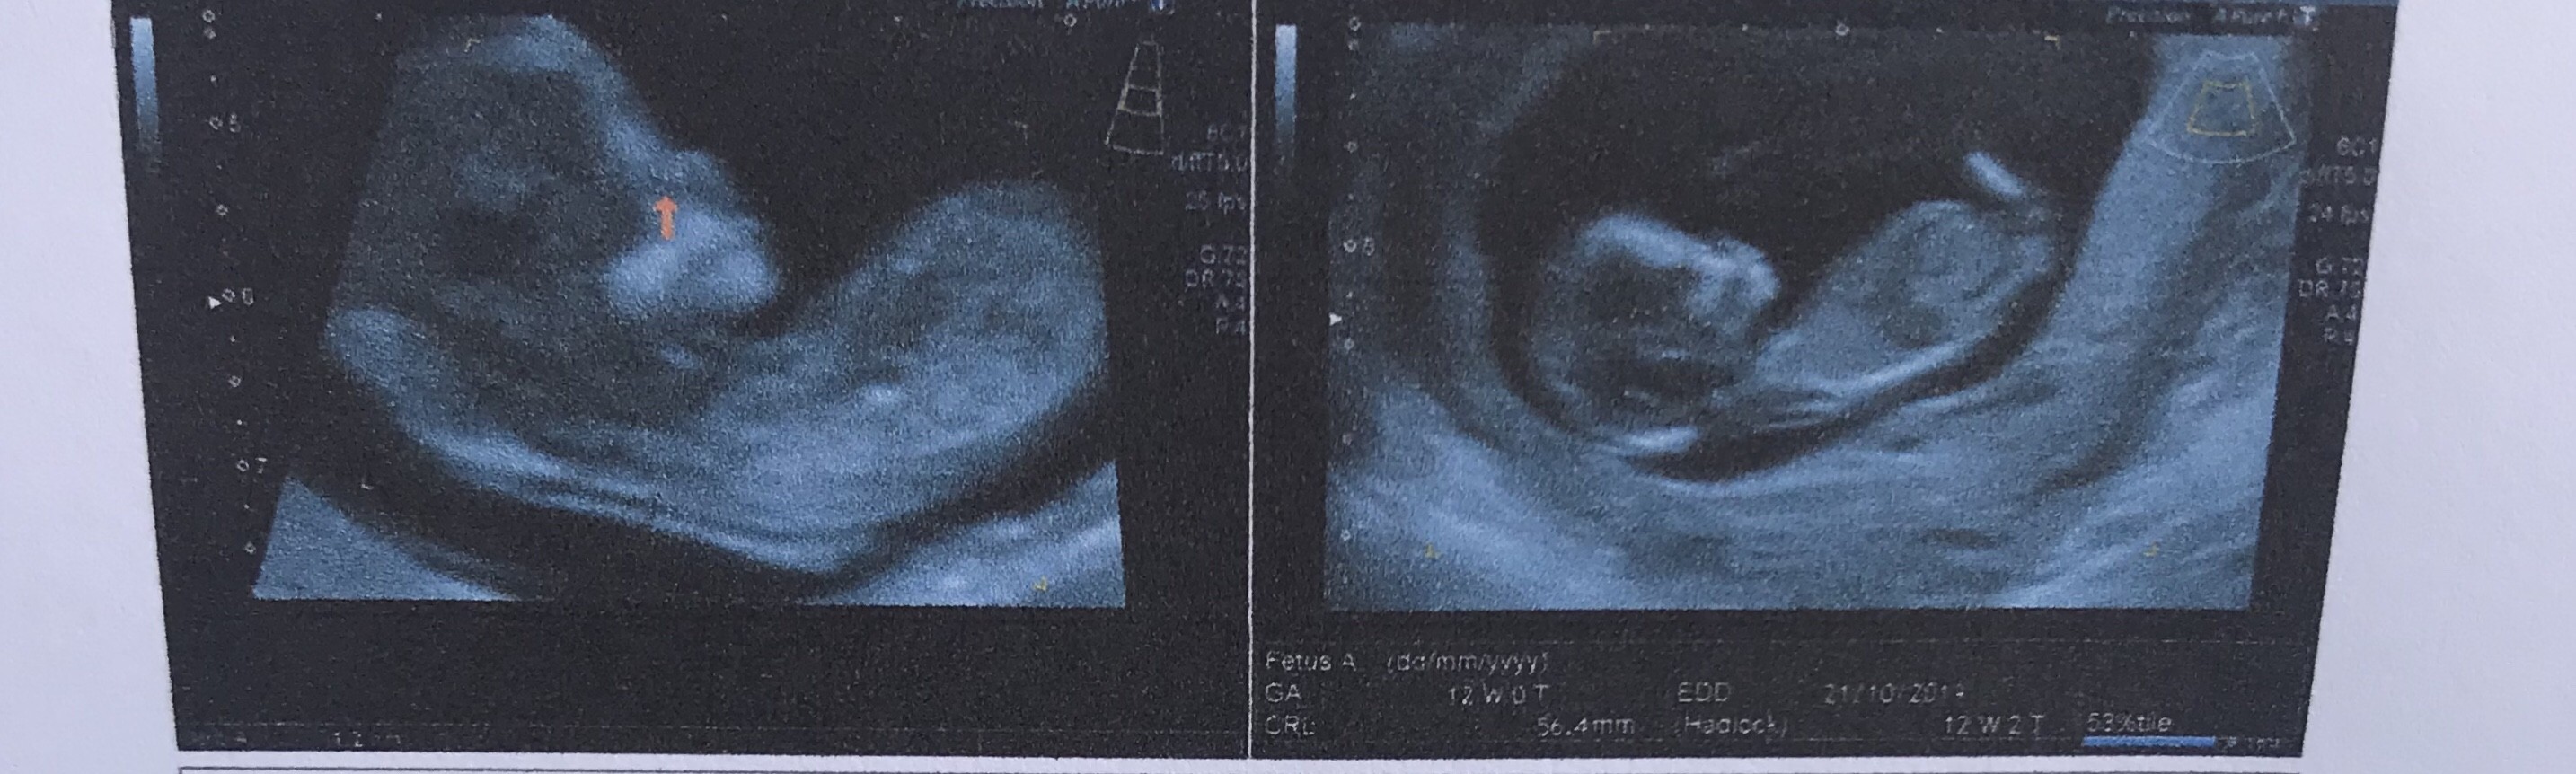

Oto jest książę przed wami

Przecudowny [emoji7][emoji7][emoji7] I widać siusiora przecież... a nie, to chyba noga [emoji6]

Jest i nasze Royal Baby! Ciotka zachwycona

Jest i nasze Royal Baby! Ciotka zachwyconai jeśli to faktycznie siusiak, a nie noga, to... Poszaleliście [emoji16][emoji3590]

Ale dzidziol [emoji7]